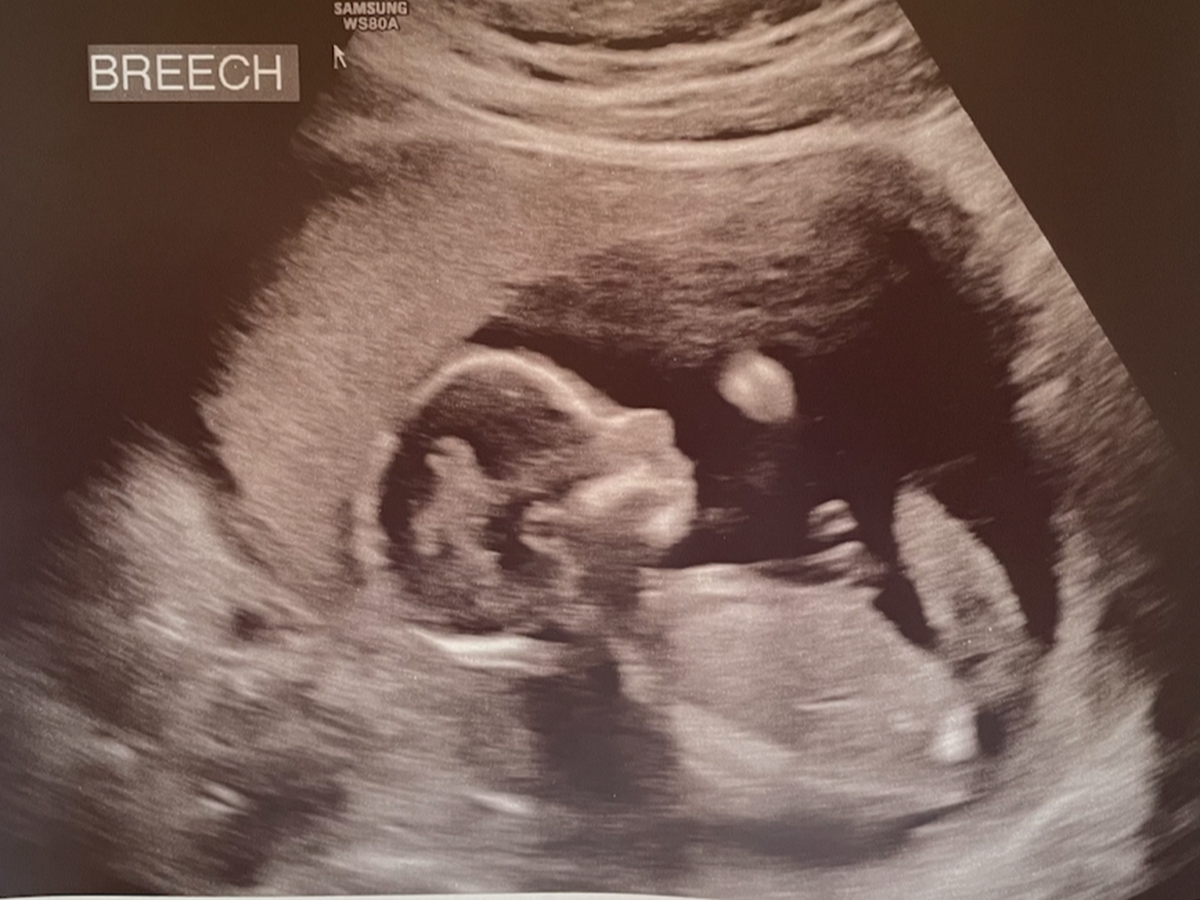

With just separating from the service my only medical coverage is with the VA and as many know that isn't the quickest source to get medical attention. After about two months of waiting we finally were able to go in for our very first ultrasound. What an amazing experience to see little tiny arms moving around and to hear a heartbeat. Everything looked great and we went on to schedule our next appointments. After about another two weeks we received a phone call for the bloodwork and our doctor recommended we came in to discuss. I wasn't sure if this was a routine thing or if it should raise a red flag but I can tell you, we were nervous. After our initial appointment we were referred the same day for a follow on appointment with a Fetal Maternal Clinic where they deal with high-risk pregnancies.

At this point we were unsure what we would be told at this doctor but more testing was done and we came to the conclusion that our little girl has a chance of having Trisomy 18. For those not sure what that means, it is a mutation in the cells that causes severe developmental issues. With that being said, our ultrasounds over the weeks began to illustrate all of the things you read on the internet which began to break our hearts. The development of Ellie's brain, facial structure, and ankles has confirmed among other tests that she does have this condition.

En este punto no estábamos seguros de lo que nos dirían en este médico, pero se hicieron más pruebas y llegamos a la conclusión de que nuestra niña tiene posibilidades de tener trisomía 18. Para aquellos que no están seguros de lo que eso significa, es una mutación en las células que causan graves problemas de desarrollo. Dicho esto, nuestros ultrasonidos a lo largo de las semanas comenzaron a ilustrar todas las cosas que leías en Internet que comenzaron a romper nuestros corazones. El desarrollo del cerebro, la estructura facial y los tobillos de Ellie ha confirmado, entre otras pruebas, que padece esta afección.